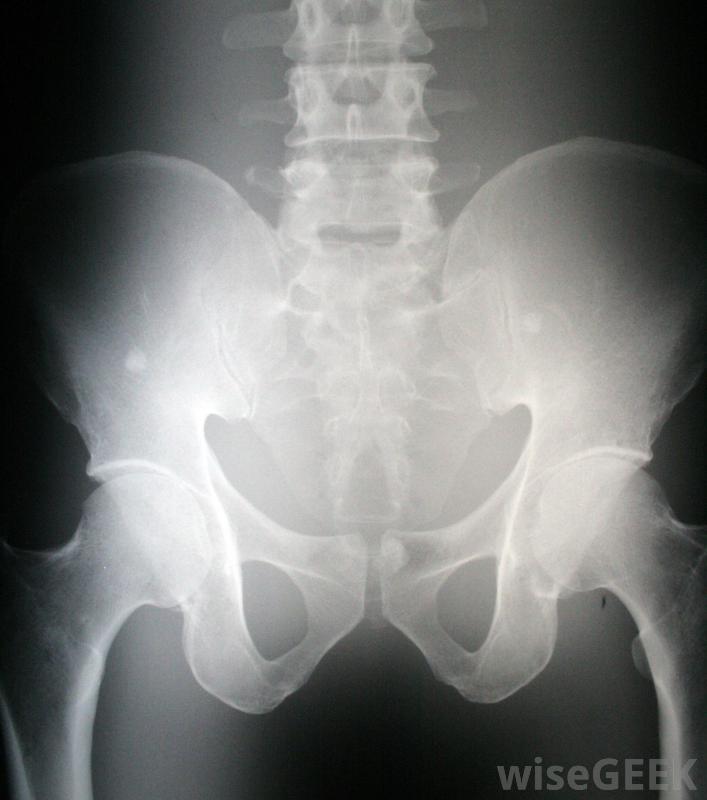

骨盆X光片。